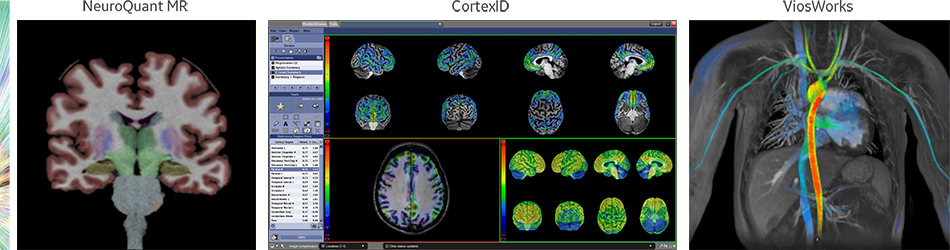

This one-stop solution enables you to imagine brain, spine, vascular and peripheral nerve anatomy with exceptional tissue contrast. These motion-insensitive techniques feature single-click auto alignment, providing the complete neuro solution from scanning to post processing.

NeuroWorks also includes Cube, our 3D volumetric imaging suite, standard with every system. This application allows you to suppress CSF and either white or gray matter to increase lesion conspicuity.